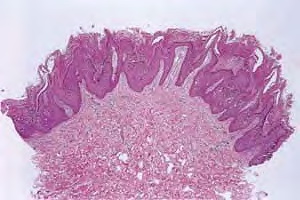

Histopathology. A characteristic histologic picture is seen in the epidermis and is referred to either as epidermolytic hyperkeratosis or as granular degeneration . It is present in bullous as well as in non bullous areas. There are variously sized clear spaces around the nuclei in the upper stratum spinosum and in the stratum granulosum. Peripheral to the clear spaces, the cells show indistinct boundaries formed by lightly staining material or by keratohyaline granules. A markedly thickened granular layer containing an increased number of irregularly shaped keratohyaline granules and compact hyperkeratosis is observed (14). When bullae form, they arise intraepidermally through separation of edematous cells from one another . The upper dermis shows a moderately severe, chronic inflammatory infiltrate. Mitotic figures are five times more numerous than in normal epidermis . Pathogenesis. Defects in keratin genes (KRT1 and KRT10) (16) are now known to be associated with this disorder. Mutations have been found in the carboxy terminal of the rod domain of keratin 1 and the aminoterminal of the rod domain of keratin 10 (17). The essential electron microscopic features are excessive production of tonofilaments and excessive and premature formation of keratohyaline granules; thus, at the periphery of the cells, numerous keratohyaline granules are embedded in thick shells of irregularly clumped tonofilaments (. The desmosomes appear normal, but the association of tonofilaments and desmosomes is disturbed, so many desmosomes are attached to only one keratinocyte instead of connecting two neighboring keratinocytes. Because of this disturbance in desmosomal attachment, blister formation takes place and real acantholysis occurs . Labeling with tritiated thymidine reveals greatly increased proliferative activity in the epidermis . It can be concluded that keratinization is both excessive and abnormal. Differential Diagnosis. Although the histologic picture of epidermolytic hyperkeratosis is diagnostic for the type of ichthyosis called epidermolytic hyperkeratosis, it is not specific for it. Hyperkeratosis is found also in several other seemingly unrelated conditions : epidermolytic keratosis palmaris et plantaris, solitary epidermolytic acanthoma, disseminated epidermolytic acanthoma, and linear epidermal nevus, usually of the systematized type. This latter entity was thought to be an entirely different condition than epidermolytic hyperkeratosis but with similar histologic findings. However, it is now known that epidermal nevi of the epidermolytic hyperkeratotic type are a mosaic genetic disorder of suprabasal keratin (l.e., point mutations of 10k alleles of epidermal cells in keratinocytes from lesional skin) that can be transmitted to offspring producing generalized epidermolytic hyperkeratosis . Epidermolytic hyperkeratosis can be an incidental finding in a variety of conditions